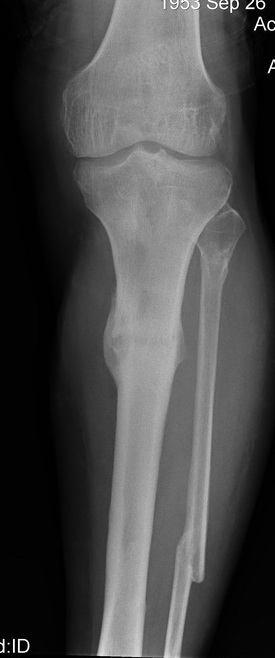

2. С аппаратом и резекцией малоберцовой кости все понятно, но почему вы предполагаете значимое укорочение, требующее транспорта? В моем случае есть признаки формирования нормотрофического (по крайней мере не аваскулярного несращения)- в приложении боковая рентгенограмма.

Качество остеосинтеза (по центрированным снимкам)я расцениваю как удовлетворительное.